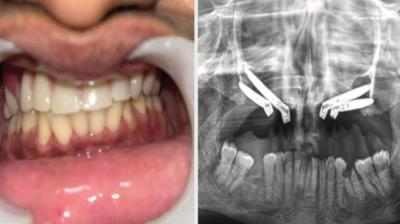

एम्स भोपाल डेंटल टीम ने लिखा इतिहास, इंटरनेशनल जर्नल में केस भेजा

6 Sep, 2025 10:00 PM IST | AMRITDEEP.COM

एम्म में जटिल सर्जरी को सफलतापूर्वक अंजाम दिया है। इस सर्जरी में ट्यूमर के कारण काटे गए निचले जबड़े को पैर की हड्डी से दोबारा बनाया गया और उसमें 13...